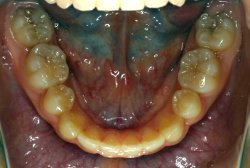

混合歯列期から治療開始した側方拡大による非抜歯症例

「配列の凸凹を治したい」という主訴で来院したケースです。診断の結果、永久歯がすべて生えそろうと、かなり厳しい叢生(歯並びの凸凹のことです)になる可能性が高いと判明しました。原因としては特に上の顎の骨が小さいため、歯を収容する容量不足になっていると診断しました。このケースの場合は、成長発育期に治療開始しますので、顎の骨を土台ごと大きくすることが可能です。

そこで、まず急速拡大装置を使用して上顎骨の拡大を行い、上顎骨の容量が拡大したことを確認後、マルチブラケット装置を使って全体の修正をする、と言う二段階の作戦をとることになりました。

この時期に使う急速拡大装置は、適切な診断に基づいて正しく使用することで確実に骨を大きくすることができます。拡大することで隙間が確保できるので、永久歯の抜歯を避けることができます。

急速拡大装置を1日1回装置の中央にある拡大ネジを、ご自身で回して頂くことで25日間くらいかけて、6mmほど拡大しました。拡大後は、上顎の前歯の隙間が広がっていることがお分かりいただけると思うのですが、土台の骨ごと広がるのでこのような隙間ができます。その後1年半くらいマルチブラケット装置を使用して、全体の修正を行いました。

結局、歯の本数を減らすことなく、すべてご自分の歯を残して正しい配列にすることができました。このケースの場合、2009年10月より拡大と経過観察を行い、2012年3月より1年2ヶ月マルチブラケット装置を装着、2013年5月に治療を終了しました。2段階で行う治療としては短期間で終了しているケースと思います。